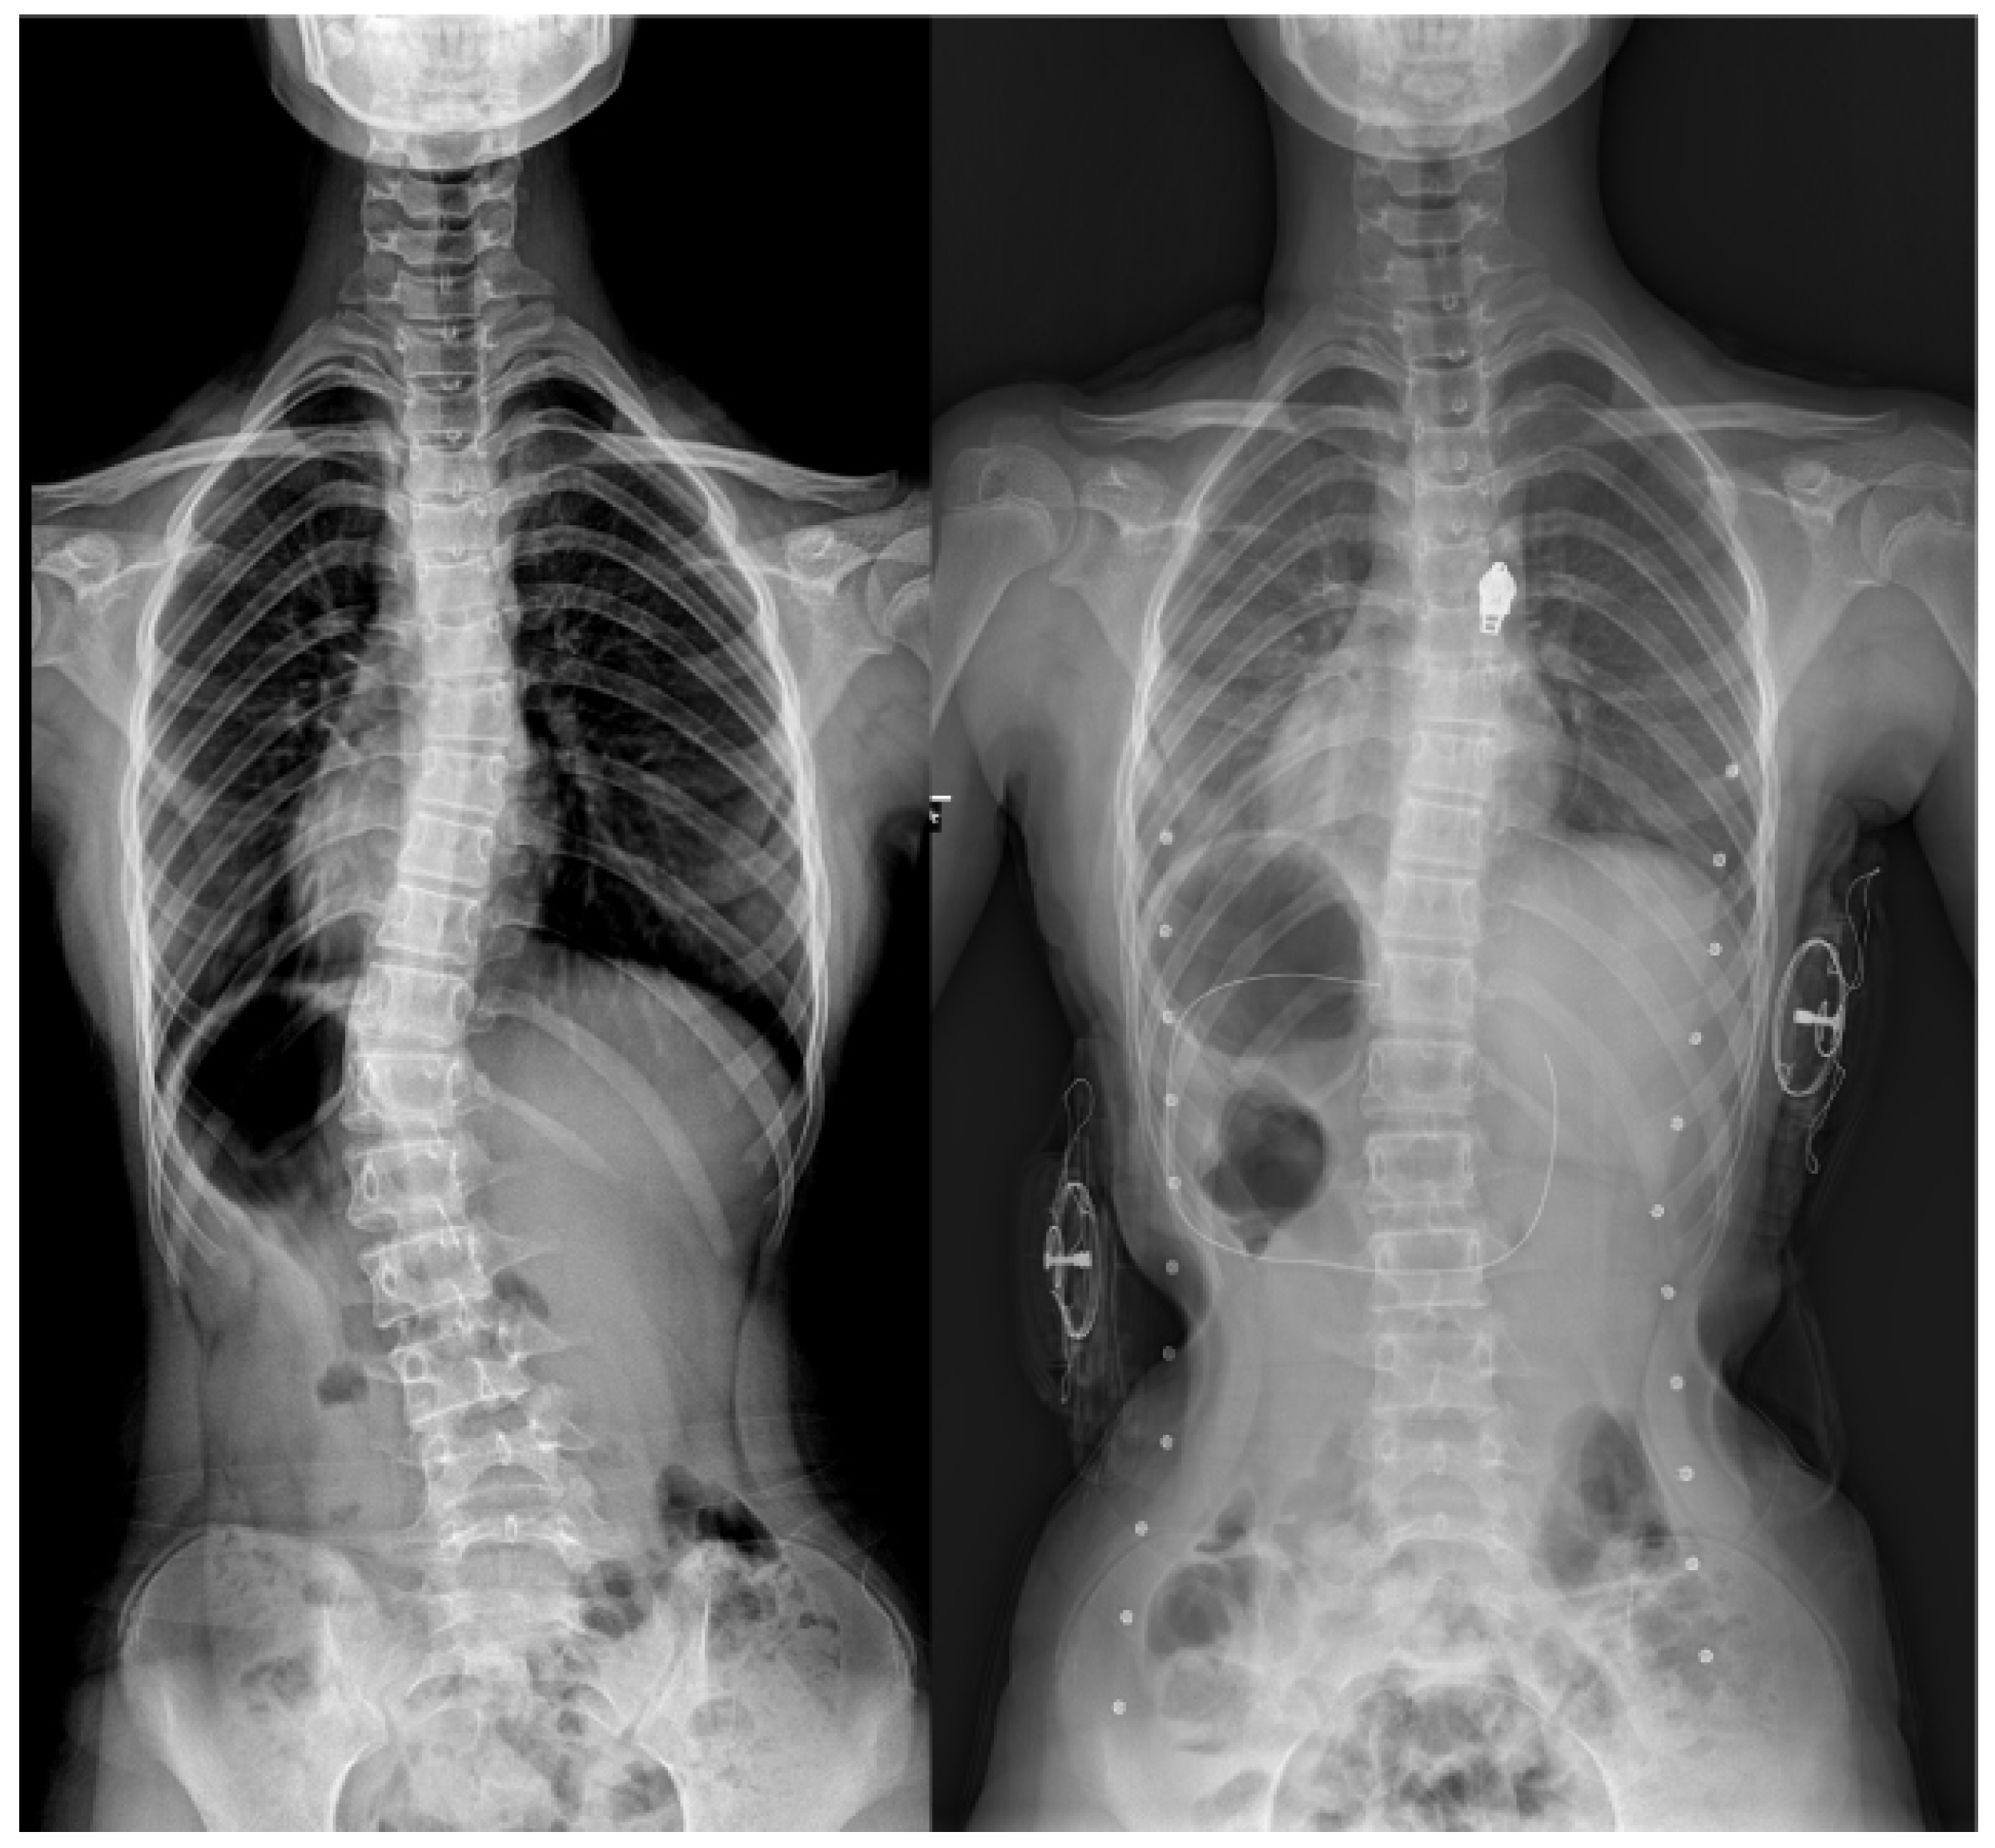

The Efficacy of a Novel Hybrid Brace in the Treatment of Adolescent Idiopathic Scoliosis: A Prospective Case-Series Study

2.2. Hybrid Brace Treatment and Follow-Up